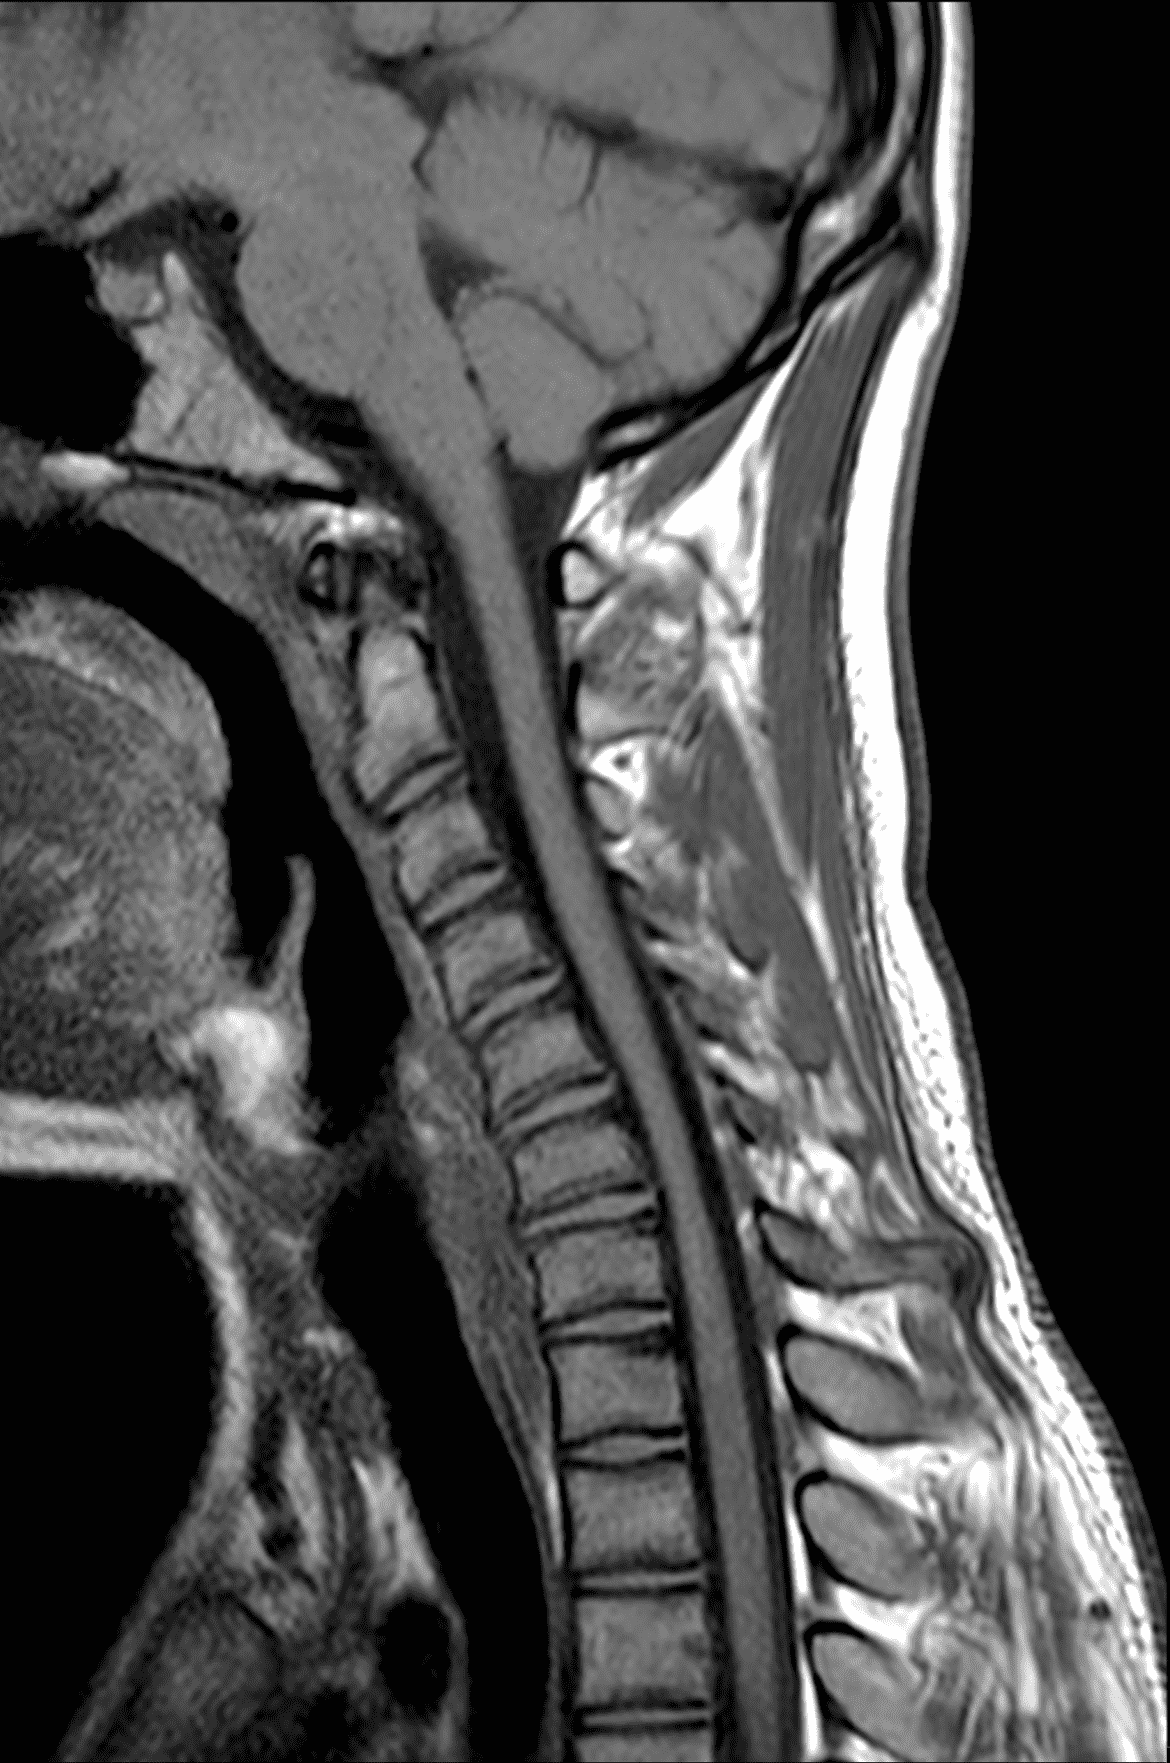

An 18 year old man presents with progressive motor wasting of right hand, progressive right hand weakness, claw-like deformity with flattening of the hand, and inability to straighten the ring and small fingers. He reports no numbness or pain. Sagittal T2-weighted (1A), sagittal T1-weighted (1B), sagittal STIR (1C), axial T2-weighted (1D), and axial T1-weighted (1E) images of the cervical spine obtained around the time of presentation are provided. What are the findings? What is your diagnosis?

Figure 2: Neutral images of the cervical spine. Sagittal (2A) T2-weighted, (2B) T1-weighted, and (2C) STIR images show mild kyphosis, an enlarged posterior epidural space with loss of attachment of the dura (red arrows), and cord atrophy at the C6 level (yellow arrow). Subtle cord hyperintensity on the water sensitive images at the C7 level (green arrows) likely represents gliosis. (2D) Axial T2-weighted image shows enlargement of the posterior epidural space, right greater than left (red arrows). (2E) Axial T1-weighted image shows an enlarged posterior epidural space (red arrows) and cord atrophy, more severe on the right (yellow arrow).